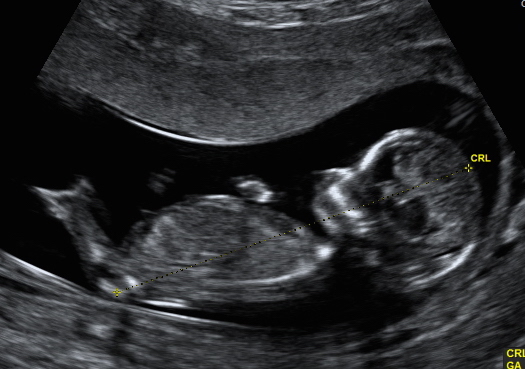

Hi, we have decided not to find out gender but i wanted to know what you ladies thought for a bit of fun while we wait! I'm not too sure if i can even see a nub in the profile but I thought someone here might be able too, also added the potty shot too, again i have no idea if you can see anything! Attachment 33072Attachment 33073